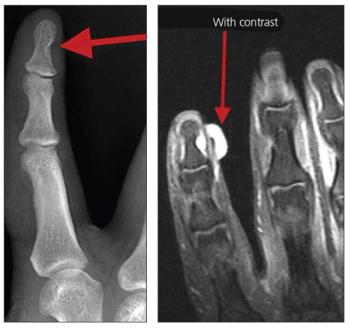

A 25-year-old man was seen in the orthopedic clinic with a complaint of severe, exquisite pain at the ulnar aspect of the distal phalanx of his dominant right index finger. The pain had been present for 10 years, but he had not sought treatment.

A 45-year-old woman presented to the emergency department with a 3-day history of an acutely painful, swollen, and erythematous thumb. Ordinary x-ray was central to the correct diagnosis.